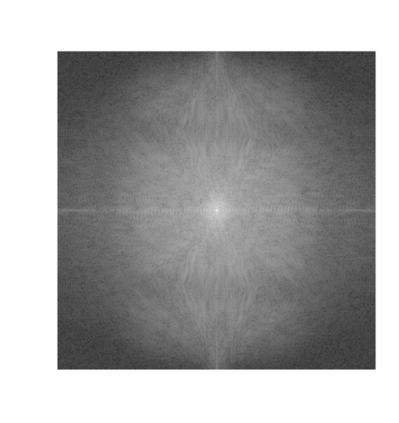

Objectives: Present a novel deep learning-based skull stripping algorithm for magnetic resonance imaging (MRI) that works directly in the information rich k-space. Materials and Methods: Using two datasets from different institutions with a total of 36,900 MRI slices, we trained a deep learning-based model to work directly with the complex raw k-space data. Skull stripping performed by HD-BET (Brain Extraction Tool) in the image domain were used as the ground truth. Results: Both datasets were very similar to the ground truth (DICE scores of 92\%-98\% and Hausdorff distances of under 5.5 mm). Results on slices above the eye-region reach DICE scores of up to 99\%, while the accuracy drops in regions around the eyes and below, with partially blurred output. The output of k-strip often smoothed edges at the demarcation to the skull. Binary masks are created with an appropriate threshold. Conclusion: With this proof-of-concept study, we were able to show the feasibility of working in the k-space frequency domain, preserving phase information, with consistent results. Future research should be dedicated to discovering additional ways the k-space can be used for innovative image analysis and further workflows.